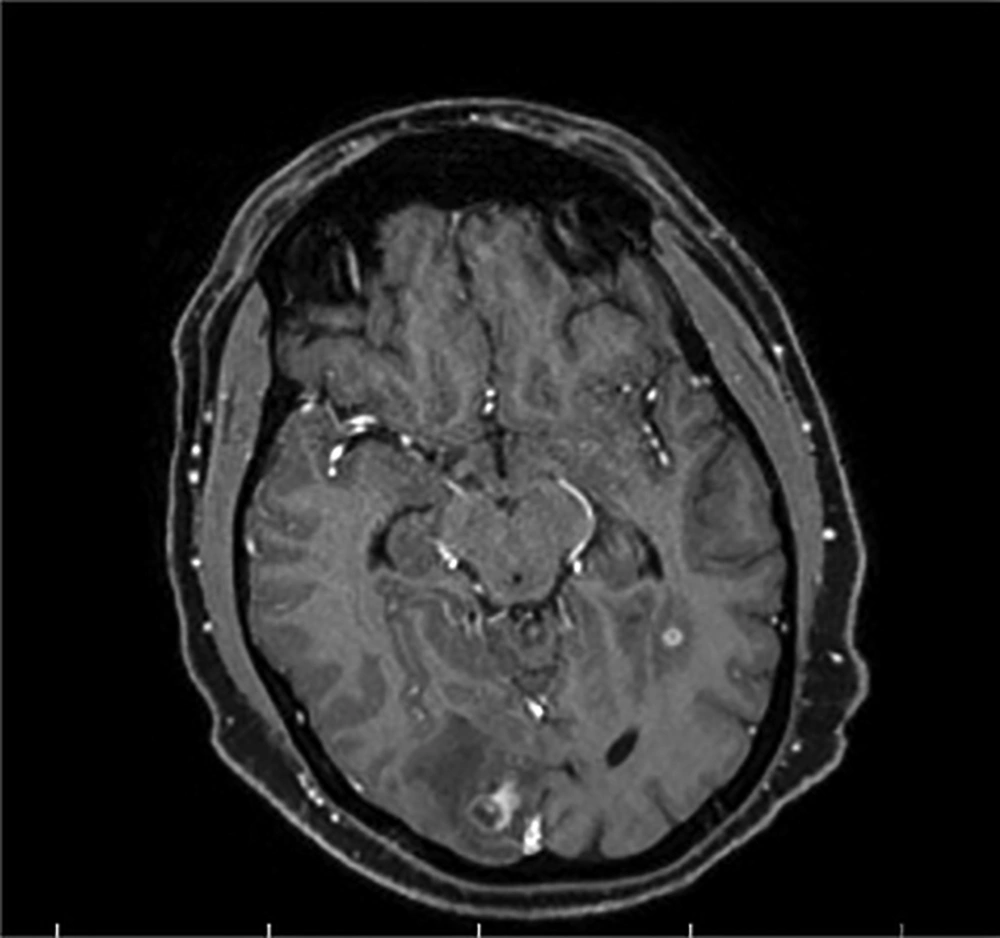

He was examined by an ophthalmologist for blurred vision and subretinal mass, optic disk swelling with hemorrhage and hypopyon, and creamy yellow exudate, as a complication of the retinal abscess, were detected. He was given an antibiotic therapy based on the CT and MRI results and the diagnosis of multiple brain abscesses (Figures 2 and 3). Due to the possibility of toxoplasma following brain and retinal abscesses, the patient received vancomycin, ceftriaxone, metronidazole, and cotrimoxazole, and the improvement of symptoms and normal state of consciousness were observed.

Brain MRI (navigation protocol; with and without GD): MRI shows multifocal vasogenic edema of the bilateral, parietal, right occipital, right temporal, left frontal lobes, and subcortical white matter lesions in both cerebellar hemispheres, indicating a multifocal abscess. No evidence of thrombosis, aneurysm, or AVM was detected in brain MRV and MRA scans.